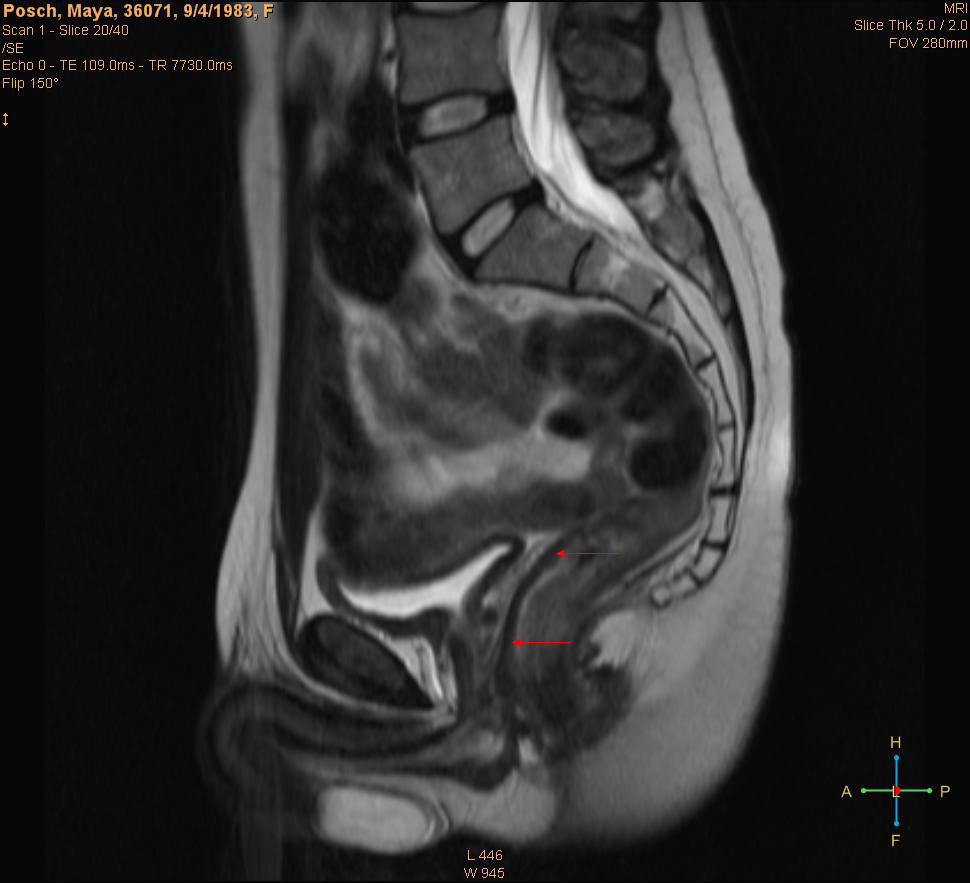

To further clarify, another scan of Maya, but this time with the suspected vagina marked:

Illustration

4: Location suspected vagina of Maya marked. From German scan.

What's clear from this scan is that in all cases the vagina is clearly visible, and the orientation and position match. There are to our knowledge no other organs or structure for either men or women which would give a similar image.